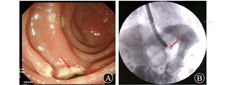

例3 患者男,26岁,2011年因脑外伤行气管切开,保留气管套管3个月余,拔管后患者呛咳明显,行胃镜检查示距门齿17~19 cm处可见高位食管气管瘘。考虑瘘口位置较高,手术创伤和风险较大,患者拒绝行外科手术治疗。2016年患者先后2次行OTSC(over-the-scope clip)吻合夹夹闭瘘口,因无操作空间,手术效果欠佳。入院时瘘口长径仍为1 cm。患者于2017年11月13日就诊于江苏省人民医院,于11月15日行经口胃镜下OverStitch缝合术,但由于高位食管气管瘘,经口胃镜下操作空间有限,手术失败。外科会诊后,于2017年11月20日行腹腔镜和胃镜联合下腹腔镜经皮胃造口,胃镜经皮、胃、食管逆行缝合高位食管气管瘘(图6)。手术过程顺利,术中使用1根缝合线,缝合6针。术中和术后无不良事件出现。总手术时间约为150 min。术后1周行上消化道造影检查,气管内未见造影剂(图7A),于11月28日出院。术后半年随访,患者自诉症状已明显缓解,复查胃镜示瘘口已闭合(图7B)。